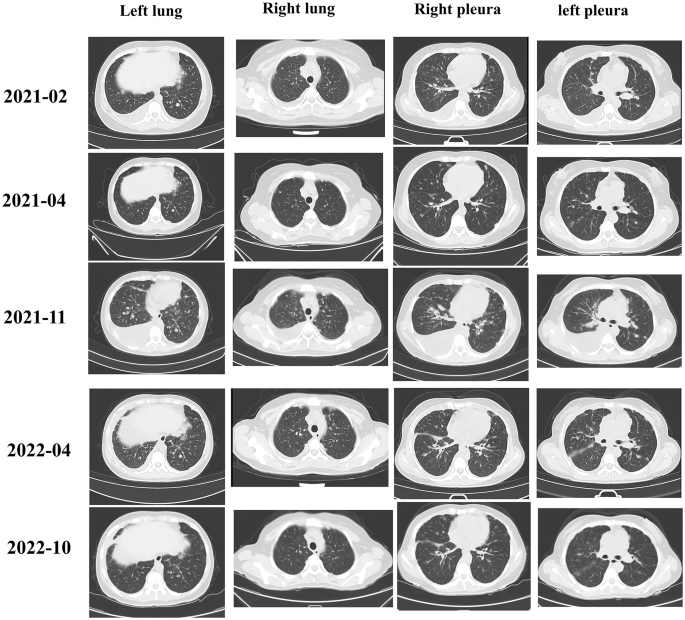

The FH germline mutations of 46 patients included 40 variants in the FH gene, including 11 insertions/deletions, 24 missense mutations, two splice site mutations, and three exon deletions (Fig. 4). In our cohort, more mutations were concentrated in exons 5, 8 and 9, accounting for 28.3%, 17.4% and 15.2%, respectively. We first analyzed the effect of immunotherapy on OS. As shown in Fig. 4, patients who received immunotherapy had a significantly better OS than those who did not (median OS: NR vs. 18.01 months, HR = 0.162, p = 0.0015). Then, the relationships between OS and the FH gene mutations were analyzed. No correlation was found between mutations in different exons of the FH gene and OS, as shown in Fig. 4. The OS of patients who harbored mutations in the kinase domain of the FH gene and those with mutations in the nonkinase domain were compared, and no differences were found. FH mutations with a high probability of causing protein abnormalities were defined as Class I mutations, including insertions/deletions and exon deletions; other mutations were defined as Class II mutations. However, OS did not differ between patients harboring Class I and Class II mutations. Then, we also explored whether the difference mutation of FH gene would affect the PFS of immunotherapy (SFig. 1). Patients with mutations in the FH gene kinase domain demonstrated a longer median PFS with immunotherapy compared to those with non-kinase domain mutations (18.9 vs. 16.1 months, p = 0.72), although this difference was not statistically significant. When comparing the PFS of patients with class I and class II FH gene mutations, patients with class I mutations also exhibited a longer median PFS, but again, the difference was not statistically significant (median: 18.9 vs. 17.0 months, p = 0.37). No association was found between the different exons of FH mutations and the PFS of immunotherapy. However, it was observed that patients with FH mutations in exon 5 had the longest median PFS, while those with mutations in exon 7 had the shortest PFS (18.9 months vs. 12.9 months).

A. Graphical depiction of FH alterations identified in our study. B. The correlation between OS and ICI treatment. The correlation between OS and C different classes of mutations of the FH gene, D kinase domain mutations of the FH gene, or E mutations in different exons of the FH gene. ICI: immune checkpoint inhibitor